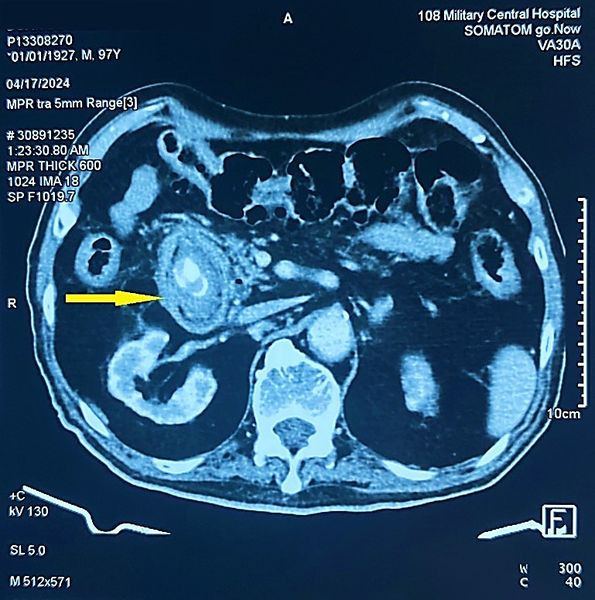

Thông qua hình ảnh chụp cắt lớp vi tính ổ bụng và nội soi tiêu hóa, các bác sĩ chẩn đoán bệnh nhân bị tắc tá tràng do sỏi mật (Hội chứng BOUVERET) kích thước rất lớn 3x5cm rò từ túi mật vào trong lòng tá tràng.

| Hình ảnh sỏi trên phim chụp - Ảnh BVCC |